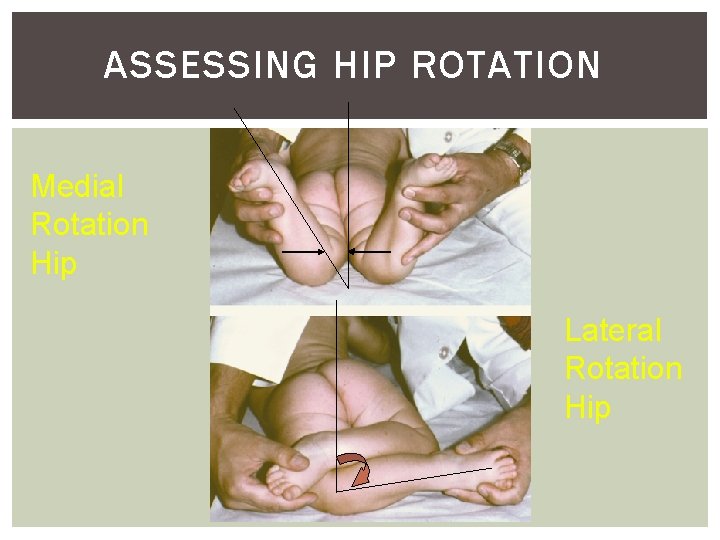

ASSESSING HIP ROTATION Medial Rotation Hip Lateral Rotation Hip